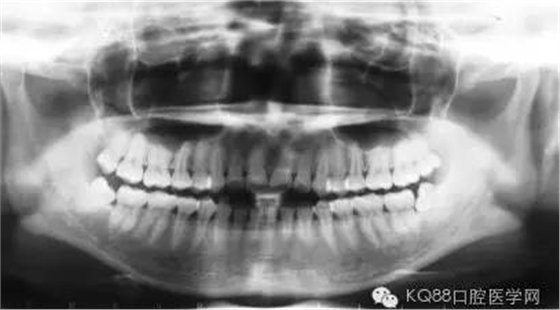

長(zhǎng)時(shí)間的牙結(jié)石堆積最后會(huì)造成牙槽骨吸收和牙周袋形成,牙周袋內(nèi)很容易聚集食物殘?jiān)图?xì)菌。這樣惡化循環(huán),最后的結(jié)果是牙齒松動(dòng)、脫落。

由于不使用牙線、刷牙方式的不正確,或者其他因素(如牙列不齊、口腔內(nèi)有不良修復(fù)體、藥物作用、激素水平的變化)的影響,也許一個(gè)人只有牙齦上的結(jié)石,沒(méi)有牙槽骨吸收的現(xiàn)象,此時(shí)只需常規(guī)的潔牙。

當(dāng)牙齦下存在的牙結(jié)石,或有牙槽骨吸收跡象時(shí),常規(guī)潔牙往往無(wú)法清除牙齦下的結(jié)石,此時(shí)需要進(jìn)行牙周刮治了。